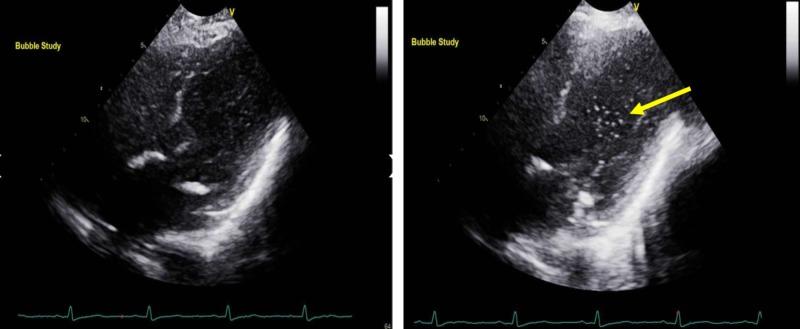

Platypnea-orthodeoxia syndrome (POS) has been defined as shortness of breath and hypoxemia in the upright position that improves with dorsal decubitus. This is a rare disorder caused by right-to-left shunts due to a persistent foramen ovale or pulmonary arteriovenous malformations. Hepatopulmonary syndrome can present with POS in the presence of pulmonary vasodilation and pulmonary arteriovenous communications in patients with liver disease. We report a case where the diagnosis of POS was made incidentally in a patient with cryptogenic liver cirrhosis. After other causes of hypoxemia were excluded, the diagnosis of right-to-left pulmonary shunt was confirmed by late opacification of the left heart chambers seen in a transthoracic echocardiogram. Interestingly, computerized tomography (CT) of the chest with contrast demonstrated a very prominent pulmonary vascular pattern extending to the periphery of the lungs. POS is a rare cause of hypoxemia that requires a high level of suspicion, and exclusion of more common causes of hypoxemia.

平卧呼吸困难-直立性低氧血症综合征(POS)被定义为直立位时出现气短和低氧血症,而在仰卧位时症状改善。这是一种由持续存在的卵圆孔未闭或肺动静脉畸形导致的右向左分流引起的罕见疾病。在患有肝病的患者中,肝肺综合征可在存在肺血管扩张和肺动静脉交通的情况下出现POS。我们报告一例隐源性肝硬化患者偶然诊断为POS的病例。在排除其他低氧血症原因后,经胸超声心动图显示左心腔延迟显影,从而证实了右向左肺分流的诊断。有趣的是,胸部增强计算机断层扫描(CT)显示肺血管纹理非常突出,延伸至肺周边。POS是低氧血症的罕见原因,需要高度怀疑,并排除更常见的低氧血症原因。